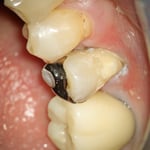

右図:圧排糸の効果で、歯の全面が見えてきました。左図に比べると、虫歯を除去したり、プラスティックを充填する範囲が極端に違ってくることがわかります。

虫歯を丁寧に除去すると、かなり深い場所まで虫歯があることがわかります。虫歯を完全に除去し、接着操作のために酸で歯面を処理します。特殊なセメントをキャリアし、象牙質に緊密な絆創膏を貼ります。(周囲の象牙質の耐酸性が向上する効果もあります)この症例の場合、欠損部にグラスファイバーのポストをたてました。(縦方向の力に耐えるため)プラスティックを充填して完了です。